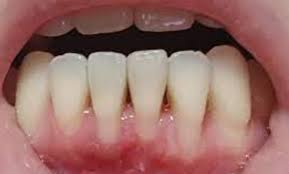

- 치주염(잇몸뼈 염증): 잇몸염증이 심해져 잇몸뼈까지 손상

| 치주염 | 잇몸이 내려앉고 치아 흔들림 | 치주치료, 잇몸수술 |